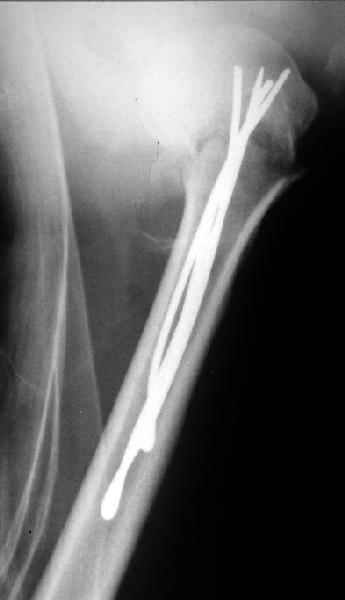

Да. У нас довольно скромный опыт такого остеосинтеза (по 2 случая - плечо и наружная лодыжка), дошли до использования самого простецкого троакара, через который мы сверлим кость и вводим 6 мм стержни, когда накладываем аппарат. Соответственно, в качестве забойника отлично работает любой стержень от аппарата Илизарова. Еще из наших туземных особенностей - страшная любовь к спицевым дистракторам, поэтому делали в нем. Результат у этой дамы неизвестен, т.к. она из области и уехала рожать сразу после остеосинтеза, сейчас прошло больше 5 месяцев...

Что-то, наверно, сделали мы не совсем оптимально, поскольку у Анатолия Федровича и его соратников как-то красивее "раскрываются" спицы в головке плеча - надеюсь, он прокомментирует и подскажет, что надо подправить.